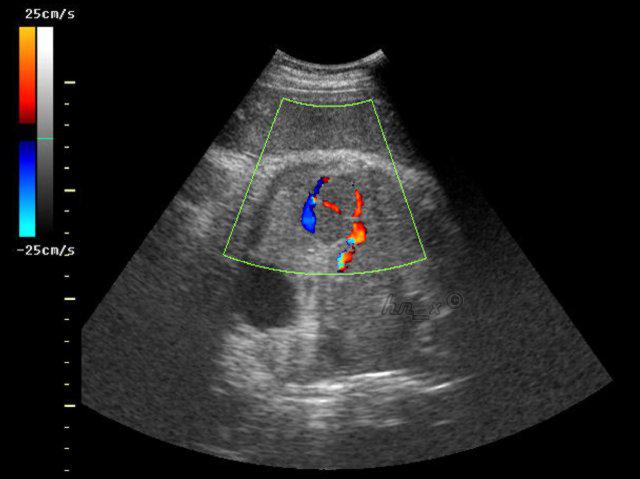

医院彩超报关单打印,效果清晰。